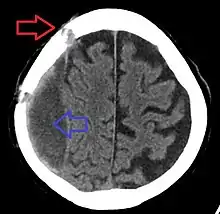

Subdural hematoma as marked by the arrow with significant midline shift

A subdural hematoma demonstrated by CT

Subdural hematomas occur most often around the tops and sides of the frontal and parietal lobes.[3][2] They also occur in the posterior cranial fossa, and near the falx cerebri and tentorium cerebelli.[3] Unlike epidural hematomas, which cannot expand past the sutures of the skull, subdural hematomas can expand along the inside of the skull, creating a concave shape that follows the curve of the brain, stopping only at dural reflections like the tentorium cerebelli and falx cerebri.

On a CT scan, subdural hematomas are classically crescent-shaped, with a concave surface away from the skull. However, they can have a convex appearance, especially in the early stages of bleeding. This may cause difficulty in distinguishing between subdural and epidural hemorrhages. A more reliable indicator of subdural hemorrhage is its involvement of a larger portion of the cerebral hemisphere. Subdural blood can also be seen as a layering density along the tentorium cerebelli. This can be a chronic, stable process, since the feeding system is low-pressure. In such cases, subtle signs of bleeding—such as effacement of sulci or medial displacement of the junction between gray matter and white matter—may be apparent.